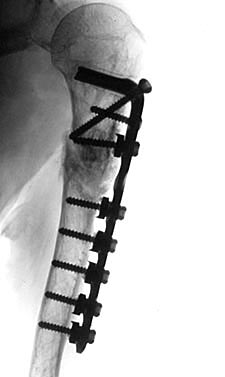

Figure 2: Older patients with ununited fractures of the diaphyseal humerus often have very poor bone quality. One method for improving the security of fixation is to use long plates. It is possible to gain extensile exposure through a number of different approaches. When the plate spans nearly the entire bone, fractures at the ends of the plates are less likely.

Long Plates

Longer plates are advantageous in a number of respects. The most obvious is that a longer plate provides stronger fixation. The larger the space between the screws closest to and furthest from the fracture site, the higher the resistance to bending loads (22) . An increased number of screws helps resist torsional loads, particularly if the screws are oriented in diverging directions(22) . Additional benefits of longer plates in osteopenic bone include a decrease in the impact of a single loose screw as well as support of a greater length of the bone by the implant so that fractures at the limit of the plate are less likely. (Fig. 2)